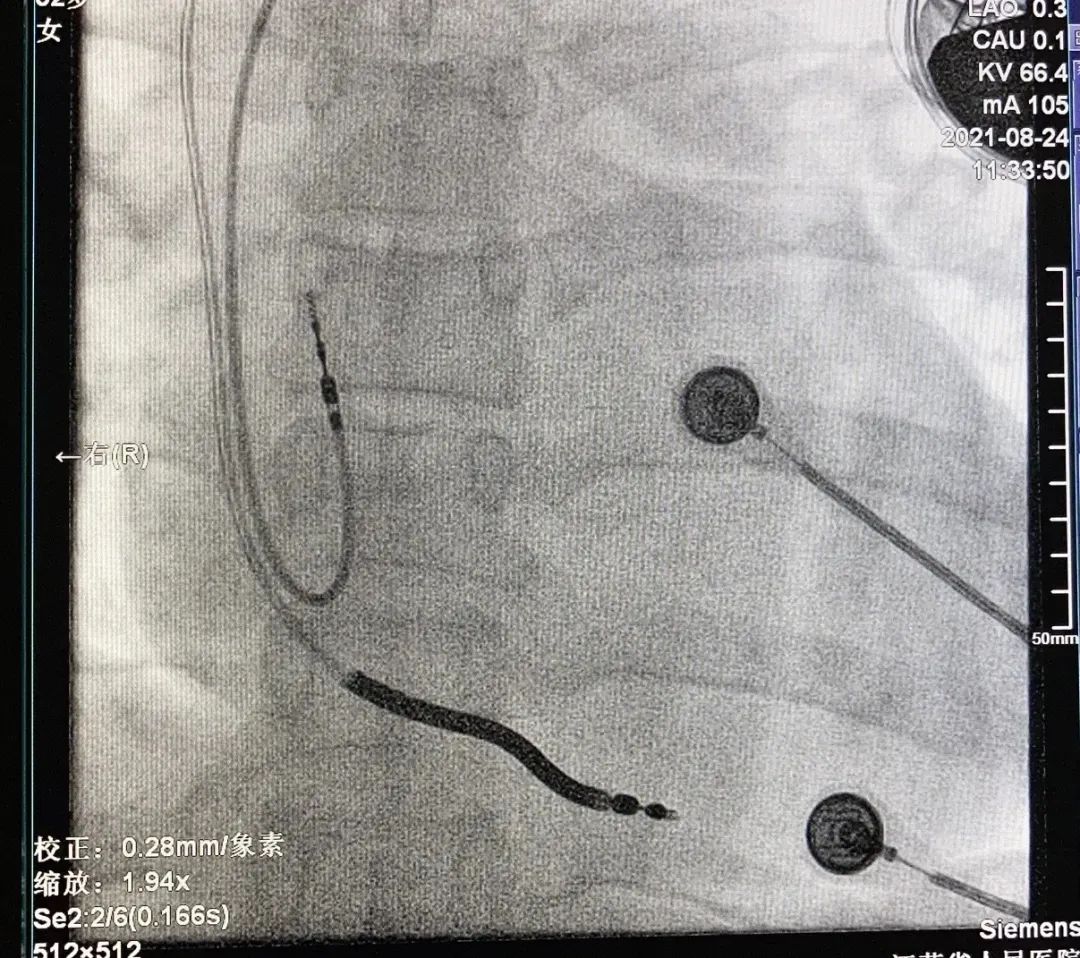

Evera MRI™ XT植入影像

2021年8月24日,南京医科大学第一附属医院陈明龙教授团队顾凯主任,顺利植入国内首批3T MRI兼容植入式心律转复除颤器(ICD)Evera MRI™ XT SureScan™。该产品为全球首款3.0T & 1.5T MRI兼容ICD,也是国内首批3T MRI兼容ICD,消除了ICD植入后的磁共振扫描限制,为中国广大心律失常患者带来了3T全身无限制部位扫描的领先技术。

考虑到该名患者较为年轻,有肺结节史,此款ICD预期寿命较长,未来接受MRI检查诊断的需求较高,所以推荐选择3T&1.5T MRI全身兼容Evera MRI™ XT 双腔ICD。手术全程仅用时60分钟,术后患者恢复良好,不仅拥有除颤器24h实时防护,也不必担心未来磁共振检查受限,出院后即可恢复健康生活。